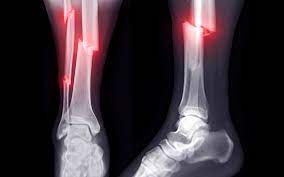

How are fractures diagnosed?

To find out if you have a fracture, your health provider will do a physical exam and ask about your injury. They will also likely order an x-ray or other imaging test to see if your bone is broken.